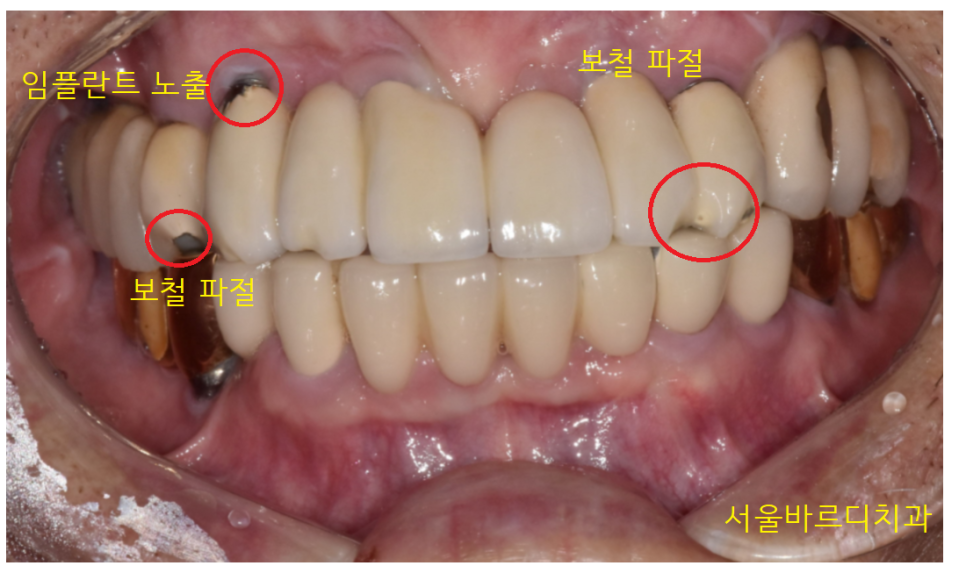

원장님 왼쪽 위가 덜렁덜렁 거리다 빠졌어요

23.06.20

환자분이 빠진 것을 가지고 오셨는데

이런!!

임플란트가 통째로 빠졌습니다.

임플란트 브릿지 형태로 묶어놨었는데

그중 1개 임플란트만 빠졌습니다.

기둥처럼 보이는 것 아래에

임플란트가 있습니다.